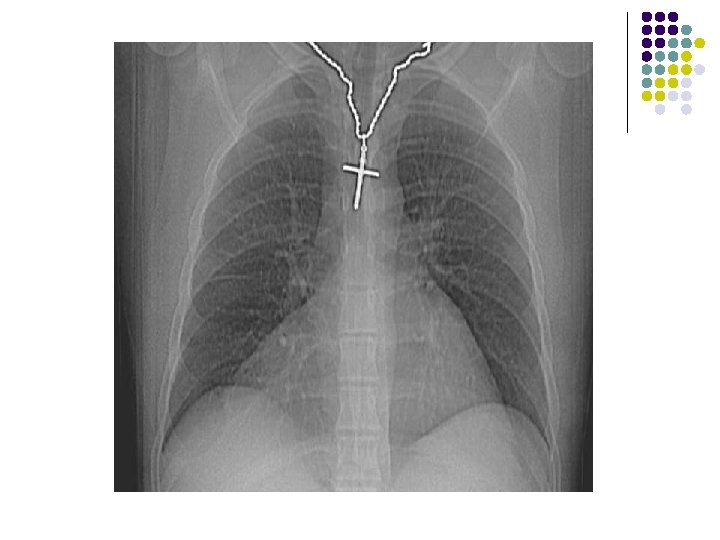

CHEST X-RAY: l A large smooth bordered opacity projecting in the right cardiophrenic angle. l Vessels and the right heart border can be seen through the opacity, which may be of fat density.